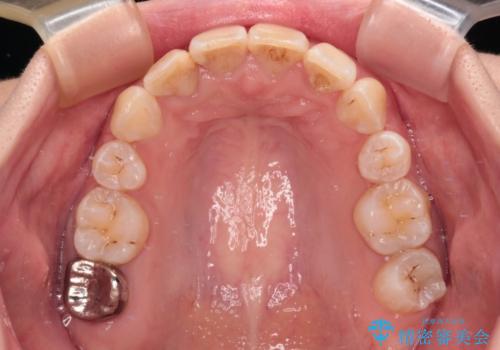

デコボコと深い咬み合わせ ワイヤー装置での抜歯矯正

- 内側に倒れ込んだ歯や下の前歯が隠れてしまうほどの咬み合わせを改善したいとのことで来院された患者様です。

下顎の叢生を解消するために抜歯が必要であり、奥歯の咬み合わせや口元の印象から、上顎も同様に抜歯と判断し、上下左右の第1小臼歯4本抜歯してワイヤー装置にて矯正治療を行うこととしました。

咬み合わせが深く、そのままでは上顎の抜歯スペースが閉じきらない可能性があったため、治療初期から深い咬み合わせを改善させるように試みました。

実際にはなかなか改善されず、当初予定よりも治療期間がやや長期化してしまいました。